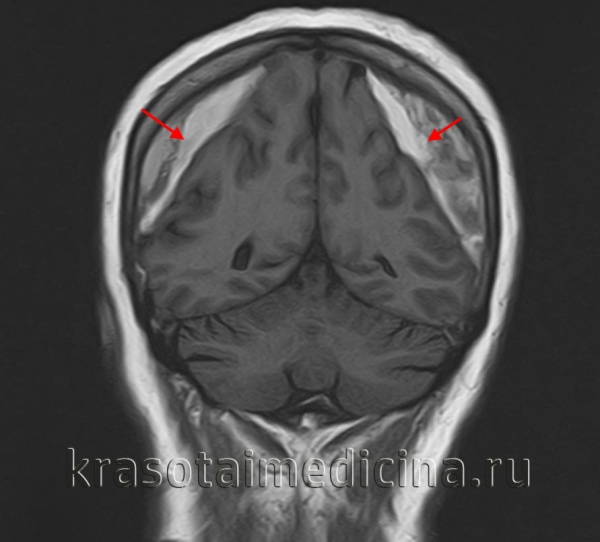

Ключевыми методами диагностики субдуральной гематомы являются КТ и МРТ головного мозга. Для острых гематом предпочтительнее КТ, которая выявляет однородную зону повышенной плотности серповидной формы. Со временем гематома разуплотняется, и через 1-6 недель она перестает отличаться по плотности от окружающих тканей. В таких случаях диагноз основывается на смещении латеральных отделов мозга в медиальном направлении и признаках сдавления бокового желудочка.

При проведении МРТ может наблюдаться пониженная контрастность зоны острой гематомы, тогда как хронические субдуральные гематомы обычно имеют гиперинтенсивность в Т2 режиме. В сложных случаях помогает МРТ с контрастированием: интенсивное накопление контраста капсулой гематомы позволяет дифференцировать ее от арахноидальной кисты или субдуральной гигромы.

Субдуральные гематомы чаще всего наблюдаются вокруг верхних и боковых поверхностей лобных и теменных долей головного мозга. Они также могут встречаться в задней черепной ямке, вдоль серпа мозга и намёта мозжечка. В отличие от эпидуральных гематом, которые ограничены швами черепа, субдуральные гематомы могут широко распространяться в полости черепа, повторяя форму головного мозга и останавливаясь лишь в области отростков твёрдой мозговой оболочки.

На компьютерной томографии субдуральные гематомы имеют классическую серповидную форму, но могут выглядеть и линзовидно, особенно в начале кровотечения. Это может затруднить дифференциальную диагностику с эпидуральными гематомами. Более надежным признаком субдуральной гематомы является её широкое распространение по полушарию головного мозга с преодолением швов черепа. Субдуральная гематома может также выглядеть как «наслоение» повышенной плотности вдоль намёта мозжечка; такая гематома может быть хронической и стабильной, а косвенными признаками кровоизлияния служат сглаженность прилегающих борозд и медиальное смещение границы между серым и белым веществом.

Хронические гематомы на компьютерной томографии могут не дифференцироваться из-за изоденсивности с мозговым веществом, что затрудняет их выявление.